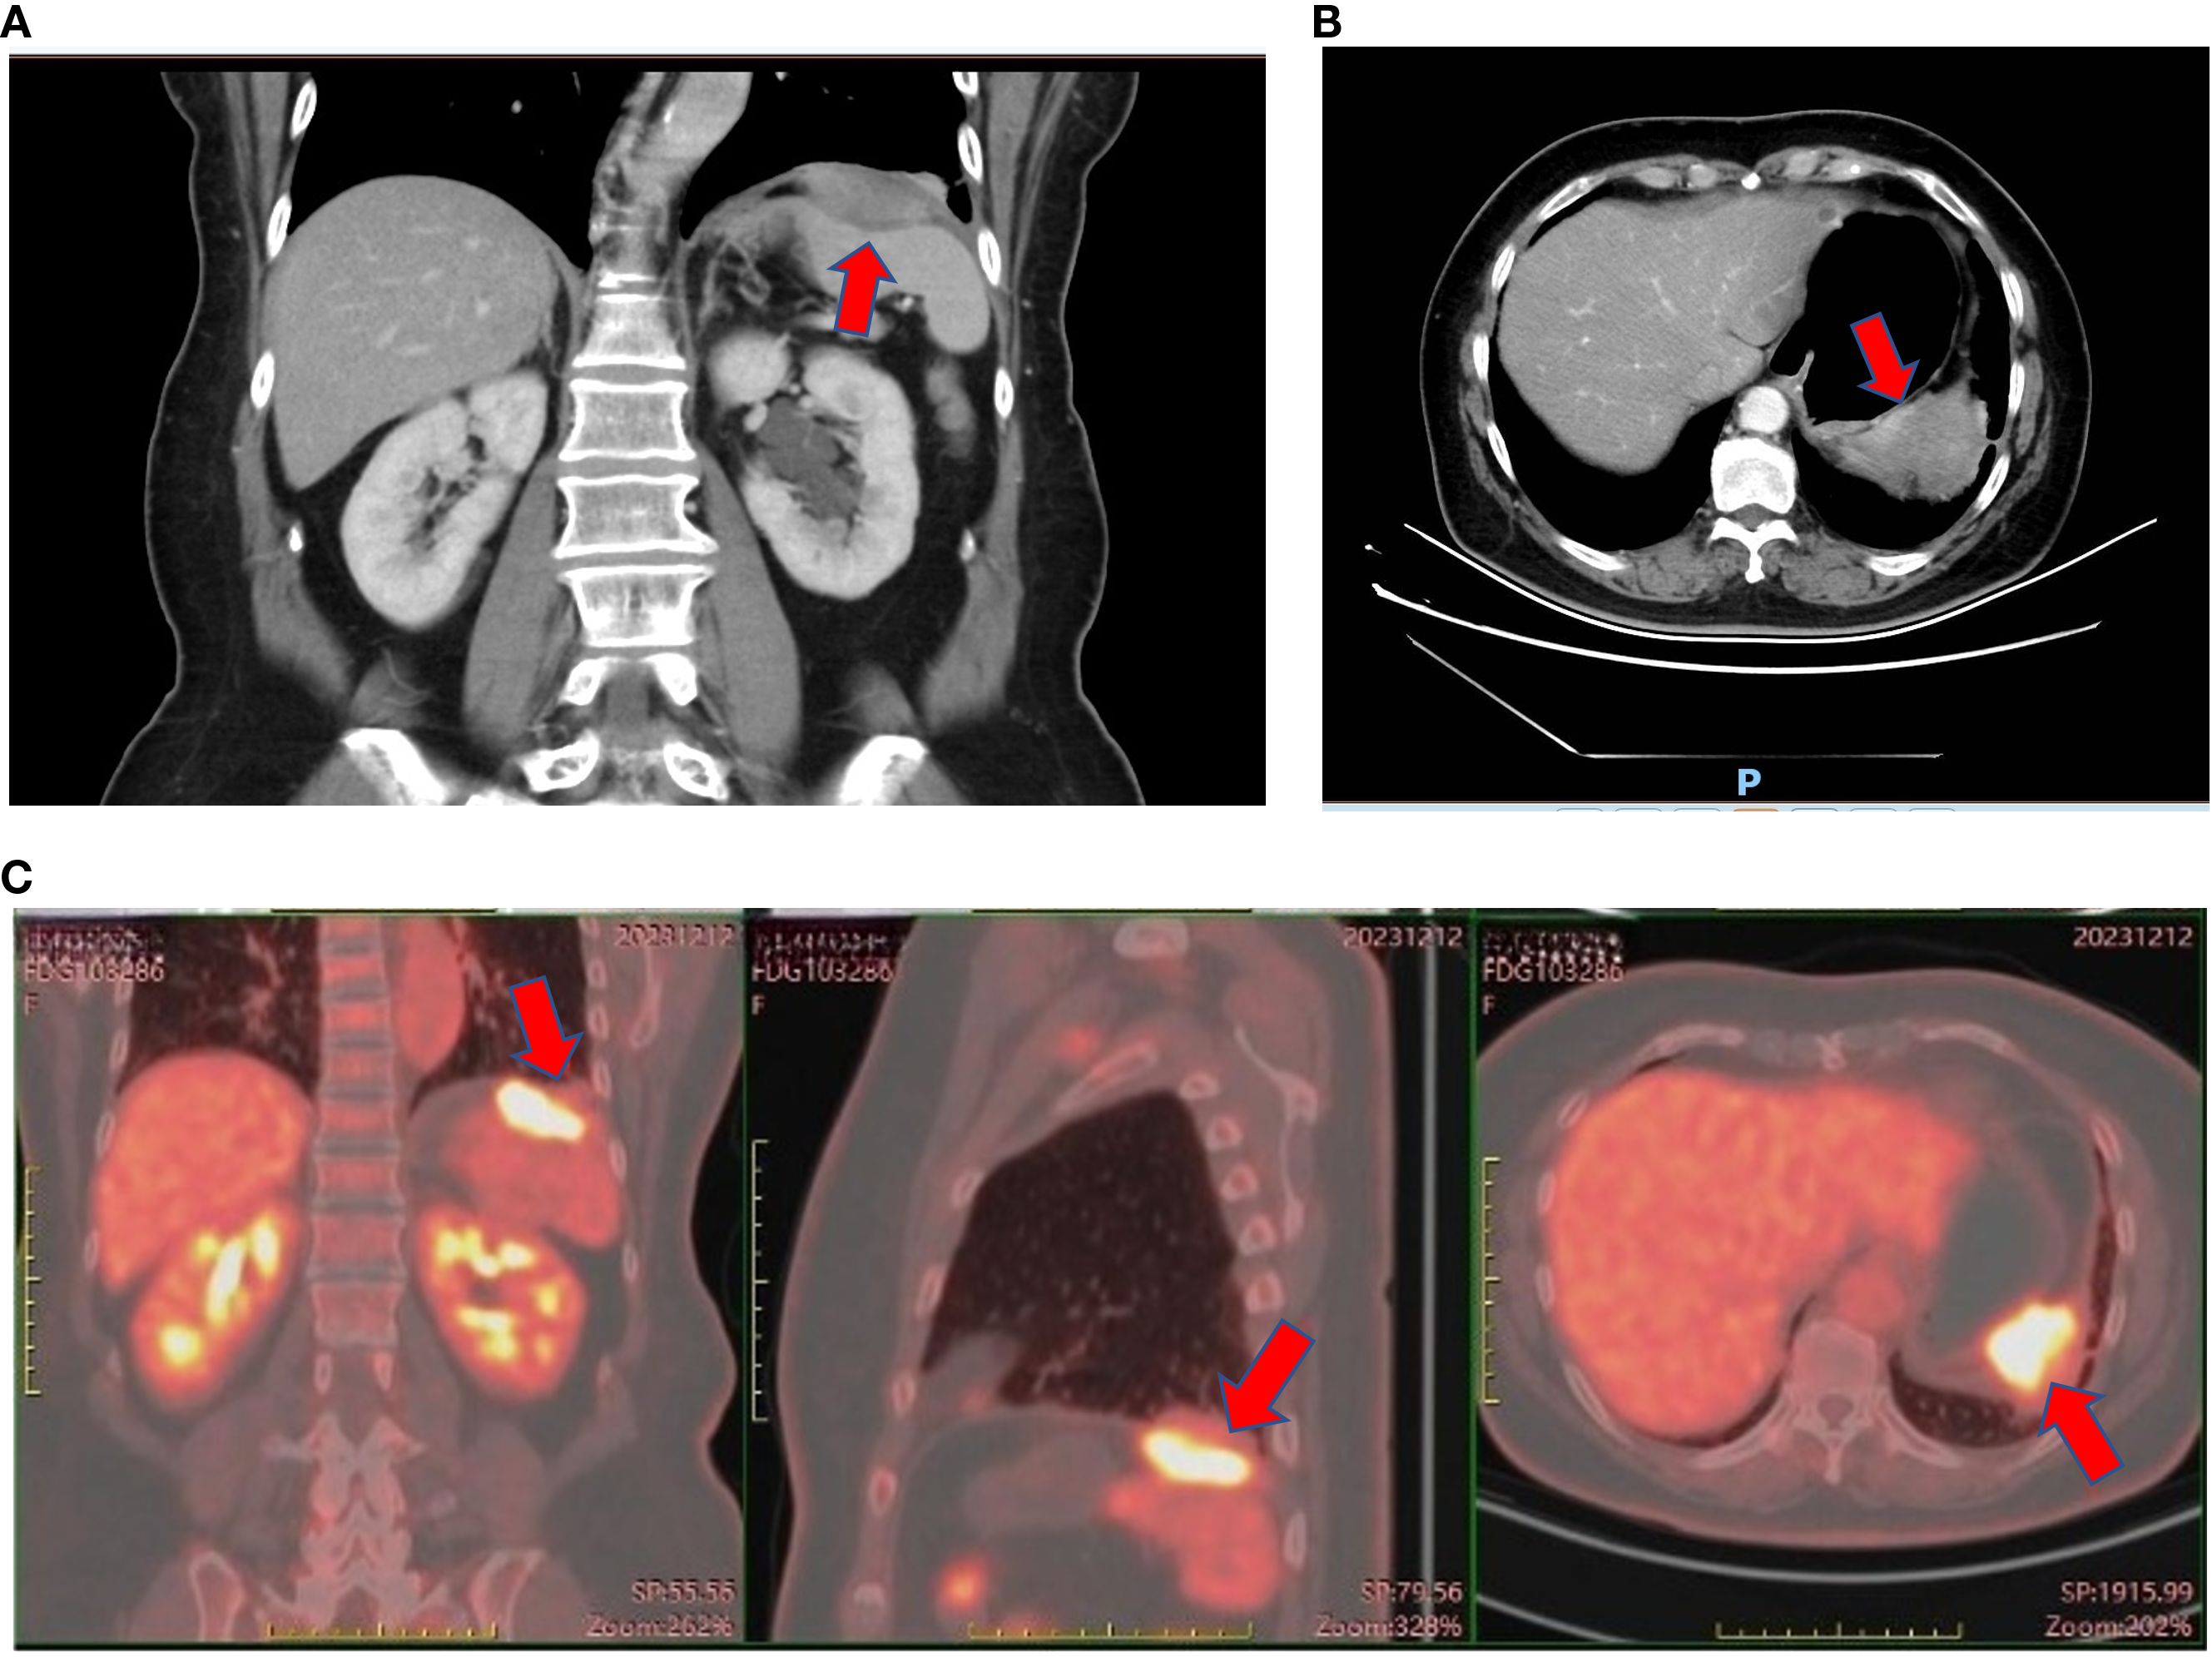

Carbohydrate antigen 19-9 (CA19-9) was incidentally found to be elevated, i.e., 56 U/ml (normal range = 0–37 U/ml), in October 2020, but no abnormal imaging findings were detected in November. Her CA19–9 had been progressively increasing since then. In May 2022, a colonoscopy showed no abnormalities. In March 2023, non-contrast abdominal CT revealed a space-occupying lesion near the spleen in the subphrenic region, but was not given attention for further investigation. The CT imaging changes are shown in Figure 1. In April 2023, gastroscopy identified a 2 cm × 1.5 cm pedunculated polyp near the cardia of the gastric greater curvature. This was pathologically confirmed as a hyperplastic polyp.

CT scans of the abdomen showing two different views from two time points. The left cross-sectional scan, obtained at initial presentation, shows no definite abnormality, whereas the right image—acquired afterward—uses a red arrow to indicate a newly developed space-occupying lesion that marks the first radiographic evidence of disease development.

Figure 1. No-contrast abdomen CT changes before November, 2023. (A) No-contrast abdomen CT on November 26th, 2020. (B) No-contrast abdomen CT on March 31st, 2023.